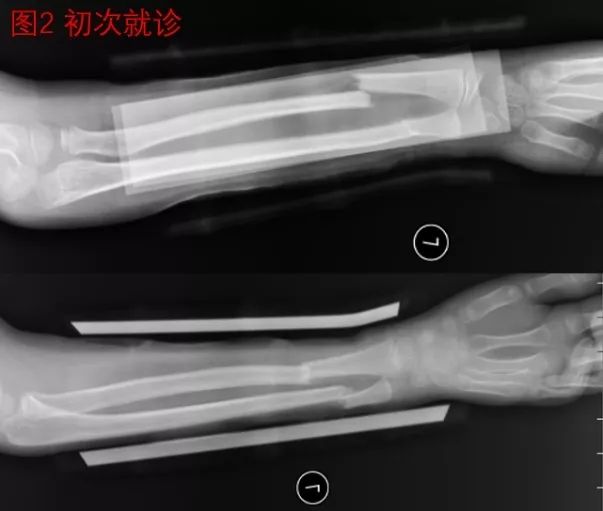

王××小朋友,在8岁运动时不慎摔伤导致前臂远端骨折,在当地医院经手法复位小夹板固定治疗。家长看了治疗后的片子,发现两根骨头断端都没有搭上,因此很难接受(图2)。去了多家医院咨询,有的医生建议开刀手术把骨头接上再用钢板钉住,家属心里又非常抗拒开刀手术,一时拿不定主意,后经同乡建议,10天后来我院就诊。我院骨科医生建议继续保守治疗,等待骨折塑形,家属采纳了建议。5年后再次复查X光片,骨折已经完全“长正”,看不到骨折的痕迹(图3)。